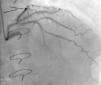

Regarding lesion type, 14 had CAV1 (38%), 12 had CAV2 (35%) and nine had CAV3 lesions (24%). During the follow-up period, six (16%) patients showed disease progression: four patients first classified with CAV1 showed progression to CAV2, and two CAV2 patients progressed to CAV3. The other patients presented a stable CAV course during follow-up. Percutaneous coronary intervention (PCI) was performed in 18 (49%) patients in the CAV+ group, in lesions classified as CAV2 and CAV3 (only focal stenosis or critical subocclusive lesions amenable to PCI). Seventeen drug-eluting stents (DES) with everolimus, sirolimus or zotarolimus, and one bioresorbable vascular scaffold (BVS), were implanted in 10 of these patients. The patient treated with BVS presented with restenosis ten months later, as illustrated in Figures 1-3, highlighting the safety issues related to these devices, which are no longer in use (Figure 4).

Patients with CAV are usually asymptomatic because of allograft denervation, and so ICA is the standard diagnostic technique.10 However, its sensitivity is limited by the diffuse nature of CAV, especially during the first year post-OHT.10,11 Intracoronary imaging techniques such as intravascular ultrasound (IVUS) and optical coherence tomography (OCT) are therefore of growing importance in the diagnosis of CAV.10,19–21

PCI is an option for patients with focal disease who present symptoms or evidence of ischemia.26 Coronary artery bypass grafting is rarely indicated due to the distal and diffuse nature of CAV lesions.22 Retransplantation is the only definitive treatment capable of improving survival in highly selected candidates.14,22

Revascularization procedures are associated with poor long-term results and are considered palliative due to the diffuse and progressive nature of vascular changes.15 In the setting of three-vessel disease, for example, PCI is associated with only 27% two-year freedom from cardiac death or graft loss.26 Small single-center experiences suggest higher (90-98%) initial procedural success but a restenosis prevalence of 35-100% for PCI alone and 20-56% for PCI with stenting during the first year.39,40 The higher restenosis rate in CAV compared to IHD is explained by the lymphoproliferative response that characterizes CAV.12 Nevertheless, in our population, PCI had very good results. DES were chosen for the majority of CAV lesions described in our series. As the treatment of established CAV is disappointing, the primary effort should be directed to early diagnosis and prevention. For this, identifying CAV predictors should be a priority.